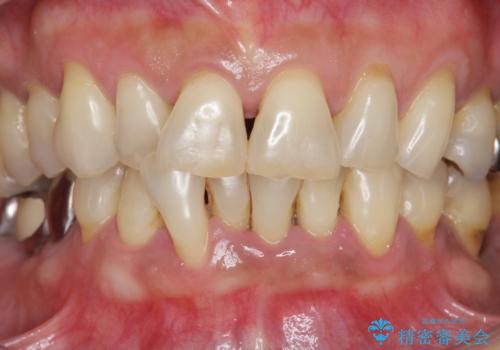

前歯のすれ違いによる歯周病を矯正治療で改善

矯正治療を行うことで、歯を削ったり(ブリッジ)、手術の必要(インプラント)なく機能を欠損部位を無くし機能回復を達成することができました。